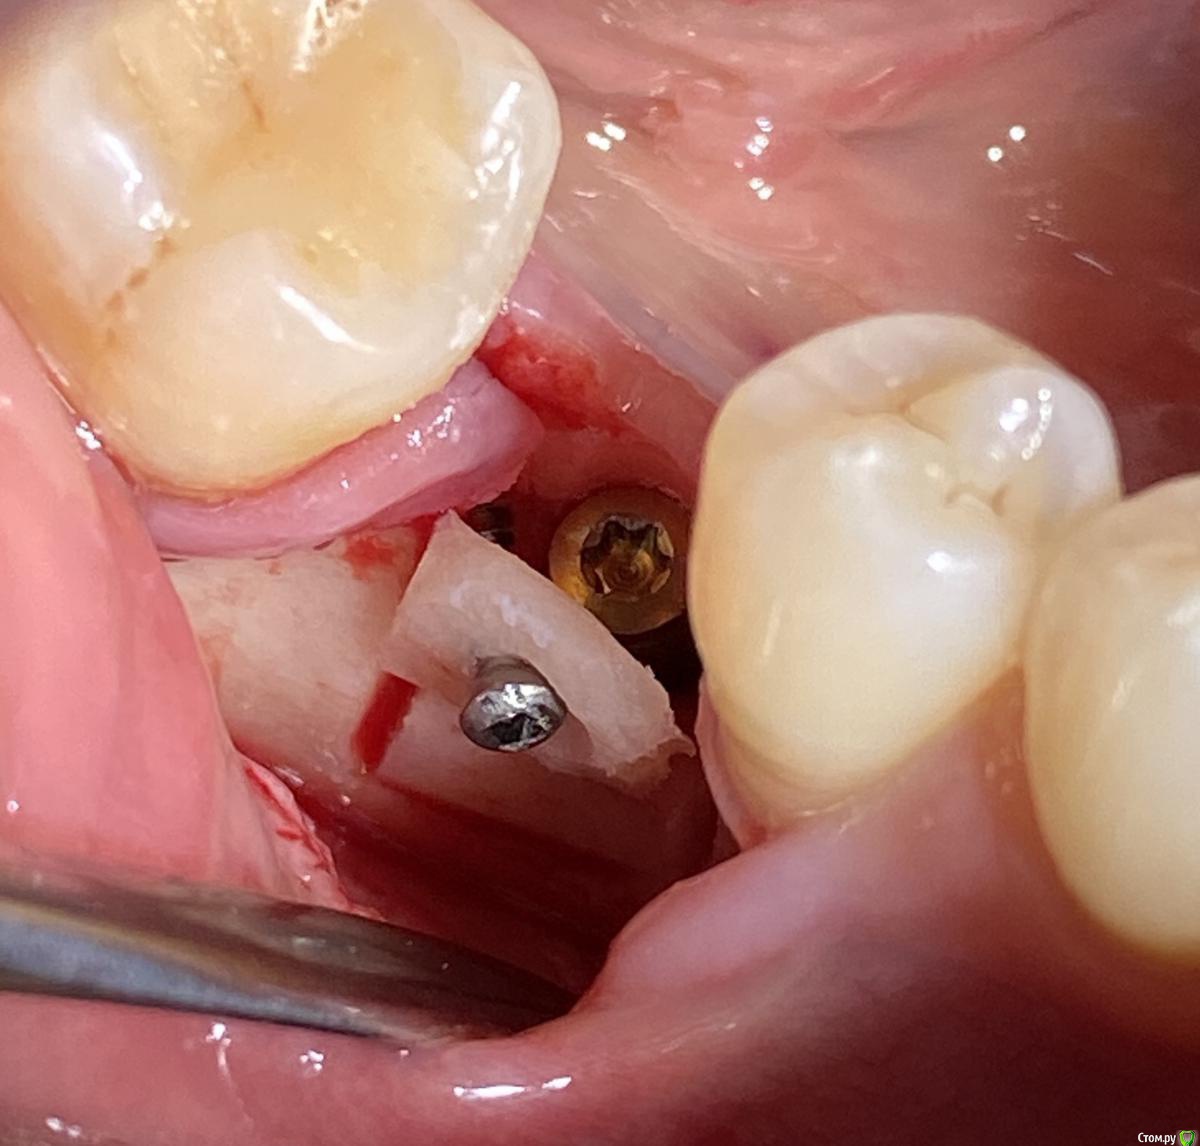

Александр07 Опубликовано 12 августа, 2020 Автор Поделиться Опубликовано 12 августа, 2020 Коллеги вот как сделали в итоге, отправляю фото 1 Ссылка на комментарий

колесников Опубликовано 2 июля, 2020 Поделиться Опубликовано 2 июля, 2020 Если не трудно поясните что значит «шайба из кортикалки») трепаном берёте из компактной кости Таблетку и одним винтом фиксируете закрывая шейку импланта Ссылка на комментарий

Марья Моревна Опубликовано 3 июля, 2020 Поделиться Опубликовано 3 июля, 2020 Если,допустим,забить такую таблетку с трепана между краем лунки и имплантом,чтоб она была совершенно неподвижна,то получается хорошее обрастание. Я такую фишку подсмотрела у Карена Аванесова,покинувшего форум со своими фотками.Он забивал кусочки кости. Ссылка на комментарий

колесников Опубликовано 3 июля, 2020 Поделиться Опубликовано 3 июля, 2020 Тут судя по снимку нет края лунки,а есть край дефекта (первый сектор) куда будет зиять шейка импланта. Зафиксировать никаких проблем тк винт и имплант в разных плоскостях и проекциях Ссылка на комментарий

Nazim_NV86 Опубликовано 4 июля, 2020 Поделиться Опубликовано 4 июля, 2020 (изменено) Между шайбой,имплантом и оральной стенкой небольшой подсыпайзинг? Или просто наглухо, и все? аутоЧерез 4мес до уровня винта может лизироваться. Должно хватить оставшегося. Если что ССТ нашампурю. формики на NC для этого удобны. Изменено 4 июля, 2020 пользователем Nazim_NV86 1 Ссылка на комментарий